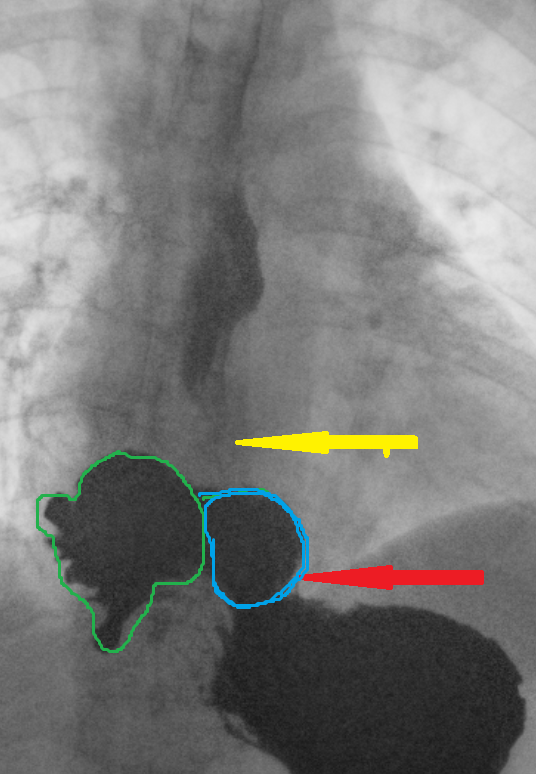

Yellow arrow — Thick-walled gallbladder with gallstones. Blue arrow — Stomach segment. Light blue arrows — Cholecystogastric fistula (Courtesy Dr. V. Penopoulos)

Plain abdominal radiographs. Small bowel loop distension. Red arrow — Radiopaque mass (gallstone) (Courtesy Dr. V. Penopoulos)